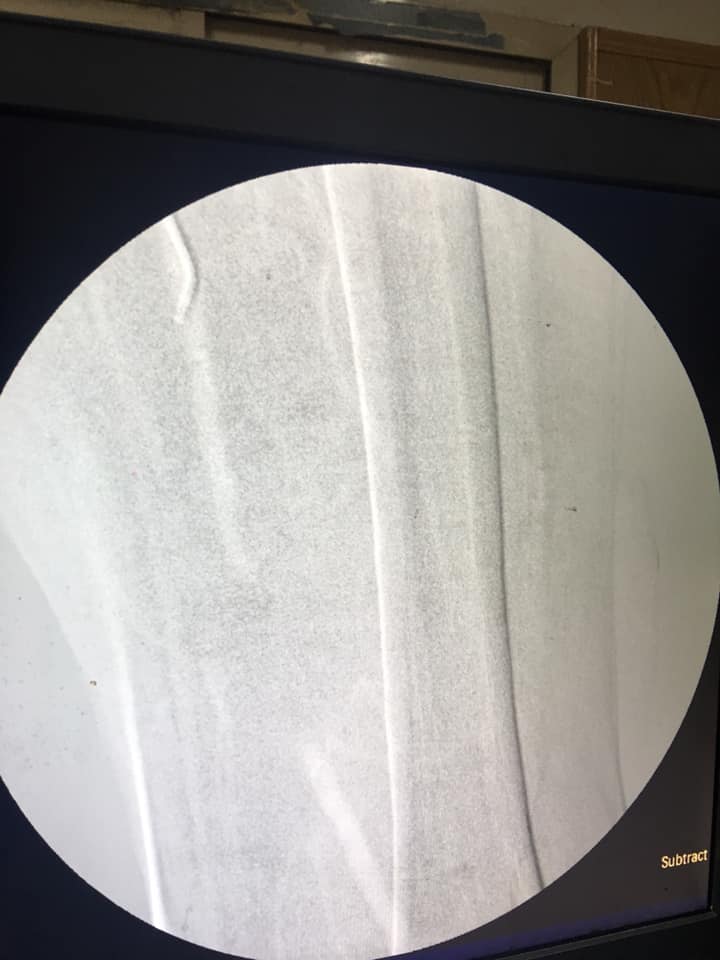

لأول مرة بمستشفيات أسيوط الجامعى استخدام تقنية ثانى أكسيد الكربون فى عمليات انسداد الشرايين

نجح فريق طبى بقسم جراحة الأوعية الدموية بكلية الطب بجامعة أسيوط باستخدام تقنية غاز ثانى أكسيد الكربون فى عمليات توسيع شرايين الساق لإحدى المرضى ، وذلك تحت رعاية الدكتور طارق الجمال رئيس الجامعة والمشرف على كلية الطب ورئيس مجلس إدارة المستشفيات الجامعية ، الدكتور حسن عبد اللطيف نائب رئيس مجلس إدارة المستشفيات الجامعية ، والدكتور سعد زكى مدير المستشفيات .

حيث صرح الدكتور مصطفى سعد رئيس القسم أن فريق طبى المكون من الدكتور أيمن حسب الله ، والدكتور أحمد حسن بكر ، والدكتور هيثم على حسن ، والدكتور محمود إسماعيل قاموا بإجراء عملية التوسيع بإجراء هذه التقنية الحديثة بدلاً من استخدام الصبغة ، مشيراً أن تلك التقنية جرى استخدامها فى عدد محدود من المراكز على مستوى الجمهورية ، كاشفاً عن انفراد قسم الأوعية الدموية بمستشفيات أسيوط الجامعى باستخدام هذه التقنية على مستوى الصعيد .

وفى سياق متصل أكد الدكتور محمود إسماعيل أحد أعضاء الفريق الطبى على أهمية استخدام تقنية ثانى أكسيد الكربون فى عمليات توسيع الشرايين لقطاع كبير من المرضى خاصة مرضى السكر الذين يعانون من انسداد فى الشرايين من قصور فى وظائف الكلى ، والتى كان سابقاً استخدام الصبغة معهم تشكل خطورة كبيرة نظراً لتأثيرها المباشر على الكلى والتى قد تؤدى فى بعض الأحيان إلى فشل كلوى ، موضحاً أن استخدام التقنية الحديثة " Co2 " حيث تعد أقل خطورة وأكثر نفعاً للمريض .